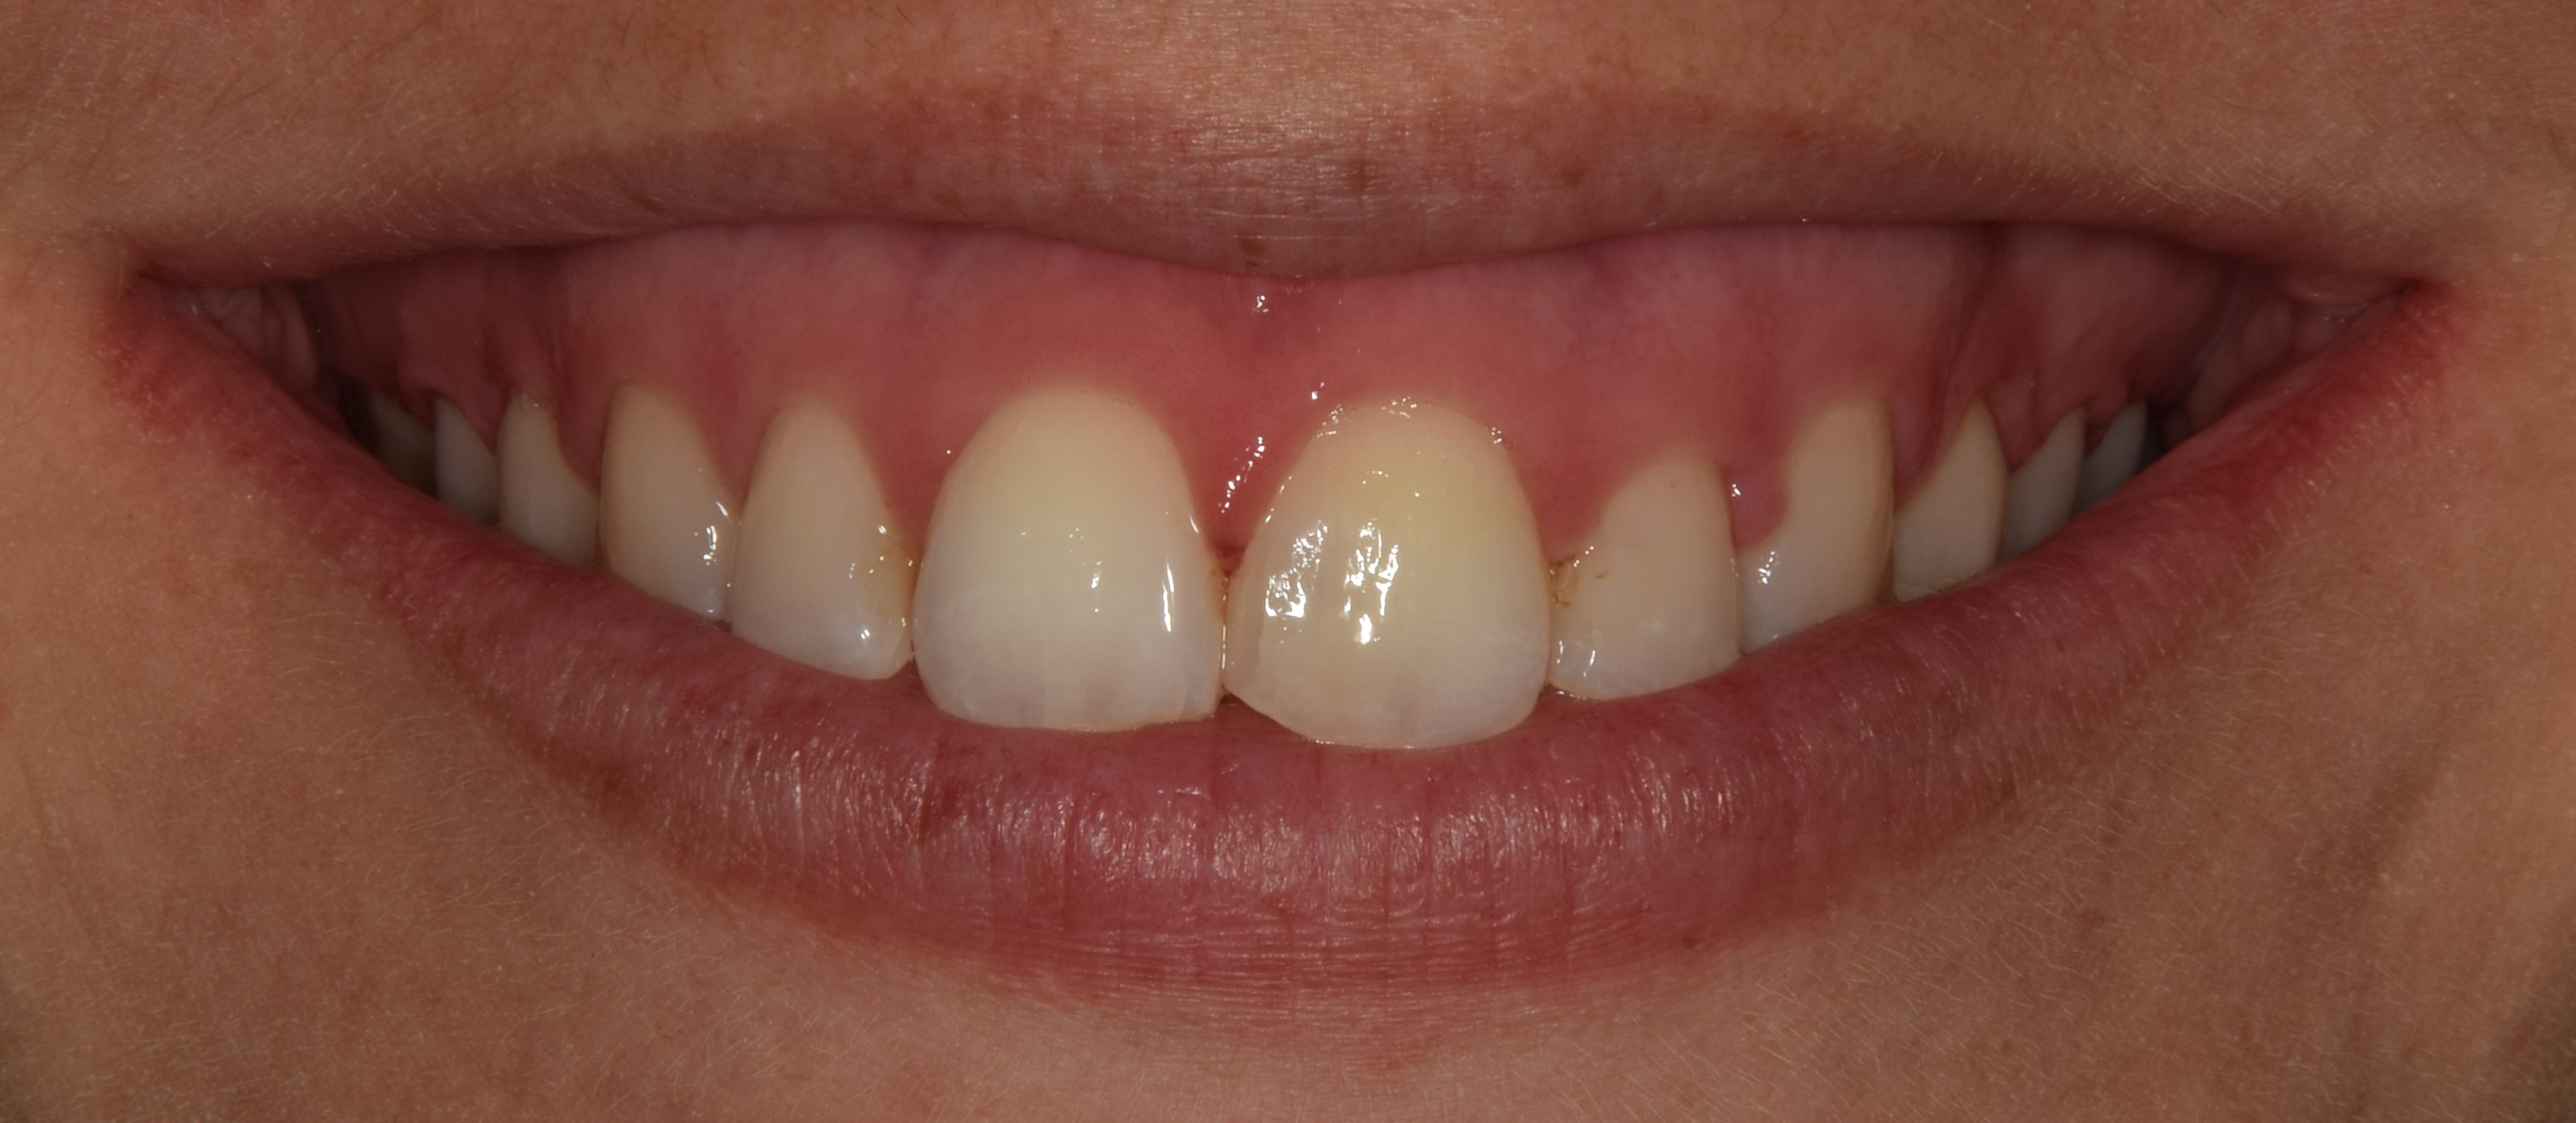

Diasthema medianum

Gyakori fogszabályozási probléma a két felső nagymetsző között jelentkező rés. Ellátását számos faktor befolyásolja. A vegyesfogazatban gyakori, legtöbbször normális jelenség, ami később spontán záródhat, ezért túlságosan korai ellátását semmi sem indokolja. Diasthemat eredményezhet például kifejezett ajakfék, számfeletti fog, kismetsző csírahiány.